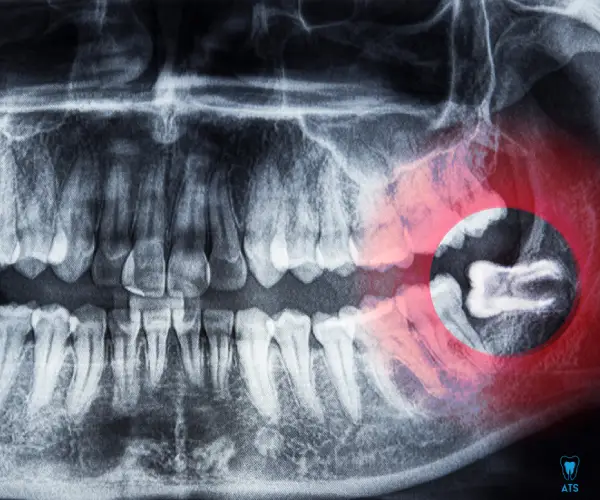

Wisdom teeth, also called third molars, usually erupt between the ages of 17 and 25. While some people have no issues, others may face problems such as pain, swelling, infection, gum disease, tooth decay, or jaw stiffness.

- Impaction – when the tooth is trapped in the jawbone or gum.

At ATS Dental Clinic, our experienced dentists carefully evaluate your condition using digital X-rays to decide the best treatment plan for Wisdom Tooth Removal treatment in Thoraipakkam.